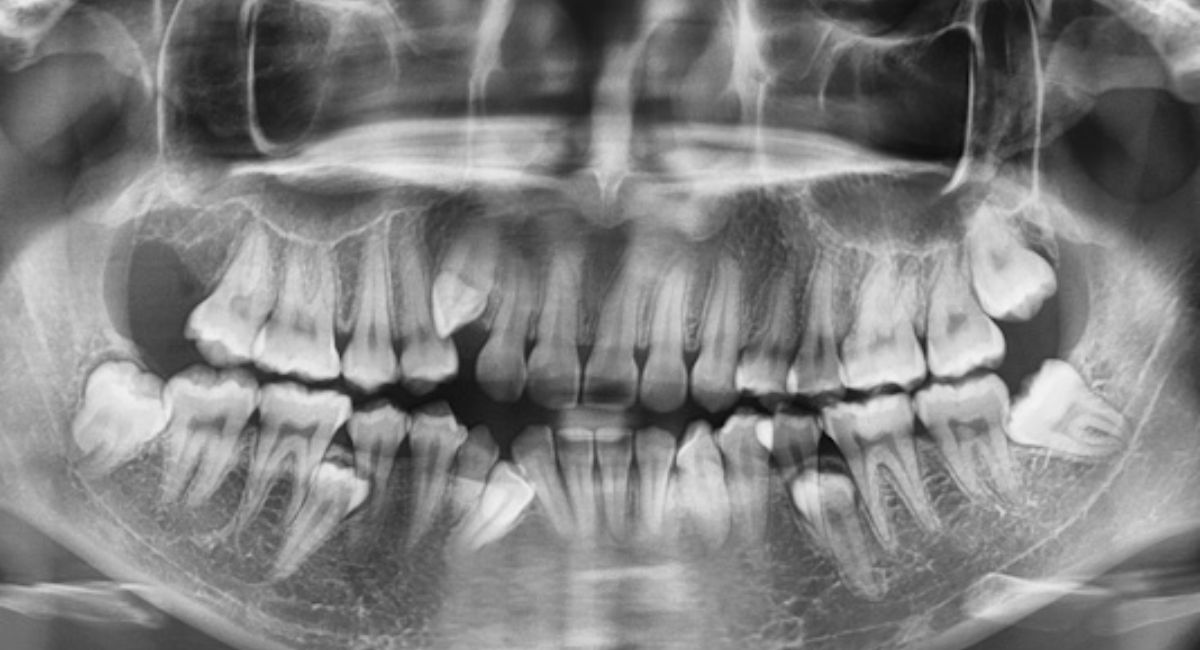

Dentists confirm the success of the removal through dental X-ray results, ensuring no dental fragments or remnants remain. If even a small part of the root stays behind, it may cause irritation or discomfort, which can feel like new wisdom tooth growth, but it’s not a real tooth.

Dentists rely on dental X-ray for wisdom teeth to see if any dental fragments or remnants are present. X-rays can detect even the smallest wisdom tooth root fragments or signs of incomplete extraction. A professional dental evaluation also includes checking for infection, swelling, or signs of irritation.

If your dentist suspects wisdom tooth coming back due to leftover roots, they may suggest a minor procedure to remove them. Regular oral surgeon checkup after extraction ensures that healing is complete and no complications are developing beneath the gum line.